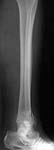

Thank you all for the kind responses. Kindly find attached the post op picture. I did an Ilizarov ring fixation which extended to the calcaneum. There was multiple small areas of partial thickness skin necrosis anteriorly and laterally which required split thickness skin graft.

Ilizarov device is a good choice, but I'm concerned about the valgus angulation (> 15degrees ?).

i would therefore, as a general rule, try my utmost to put in more wires in the distal fragment to gain a good hold + compression across the fracture site adds a lot to the stability of the frame. usually, in stable configuration of fractures, like your patient has, the calcaneal fixation then becomes redundant. you would need to compress this fracture further, judging from the xrays